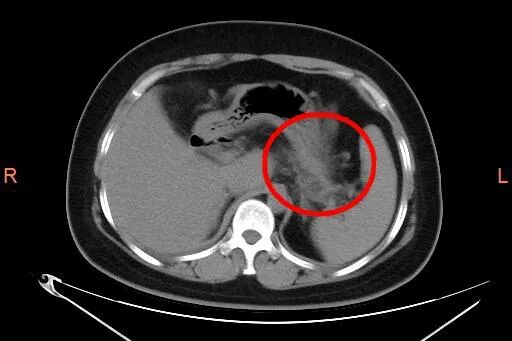

医生经过查体和腹部CT检查

患者符合

急性胰腺炎指征

重症高脂血症性急性胰腺炎